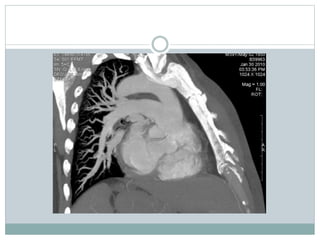

These two CT images show a large pulmonary embolus in the left main

branch of the pulmonary artery. On the left is a lateral view of the artery and

on the right is the anterior view of the same artery.